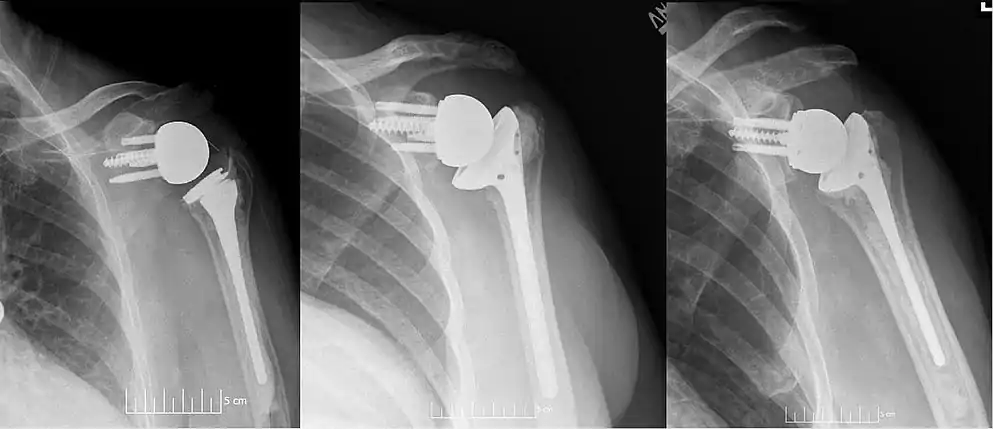

![]() Plain film radiograph in anteroposterior (AP) view of a right shoulder status post reverse shoulder arthroplasty using a prosthesis with a lateralized center of rotation.  | |